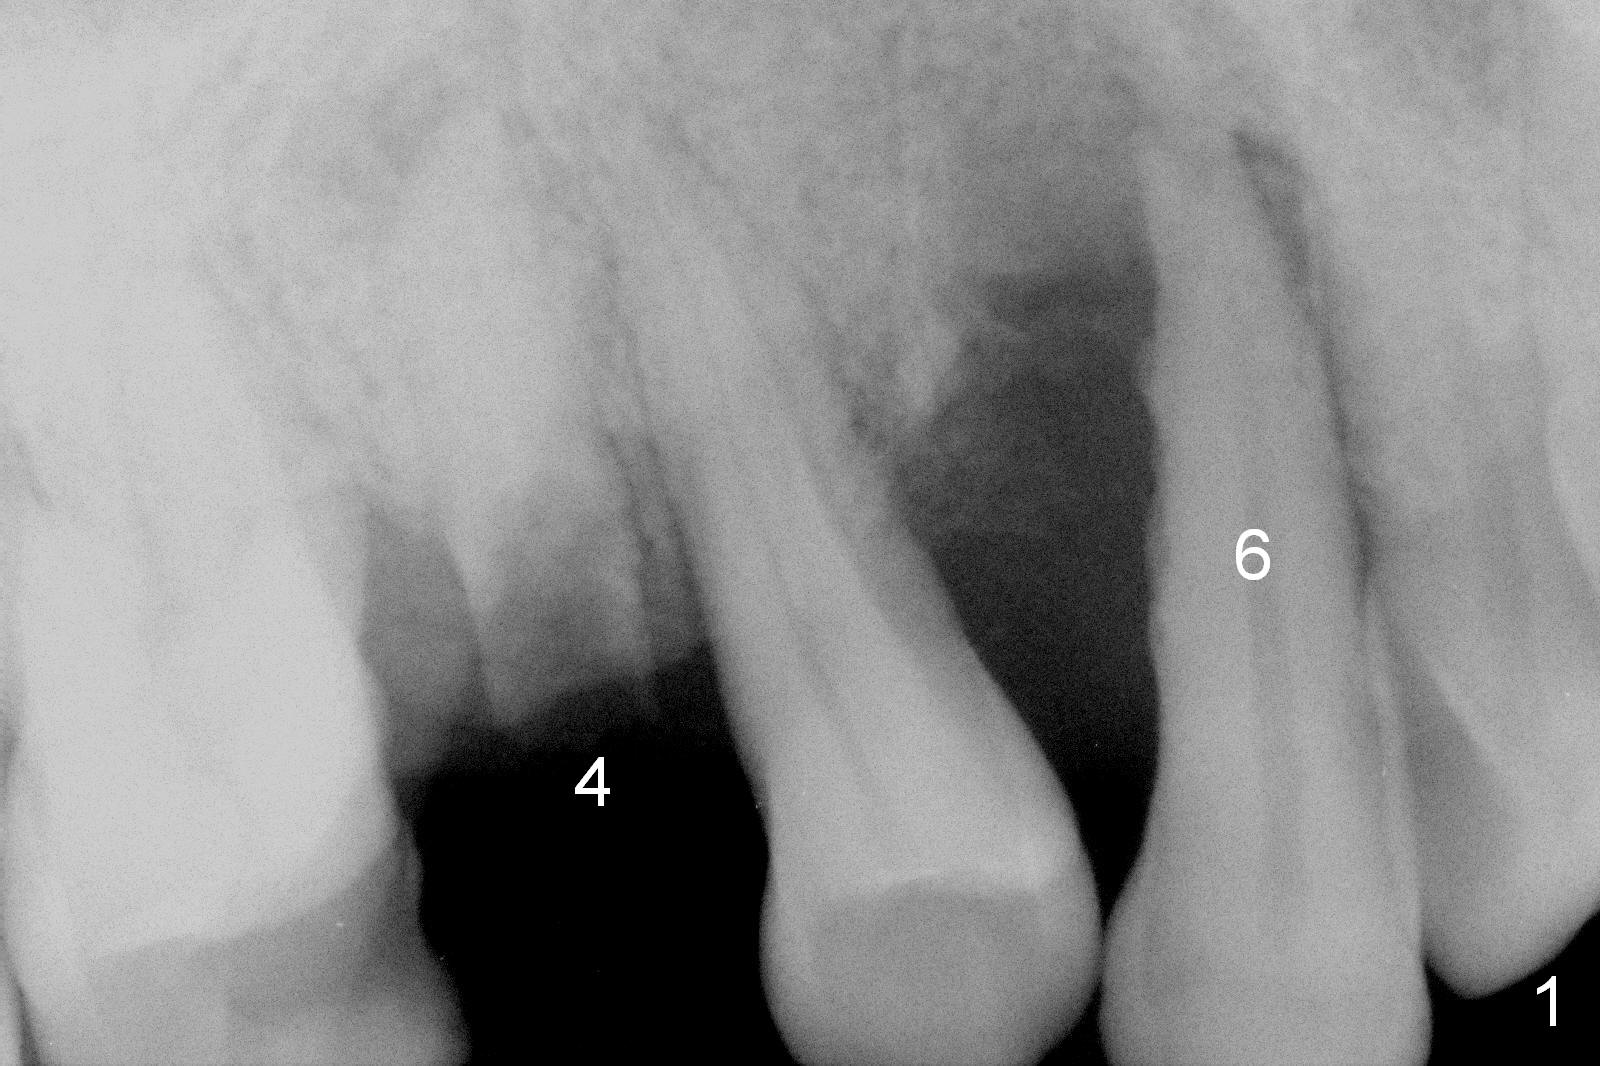

A 62-year-old man (CZ) has had chronic periodontitis. A month ago, five immediate implants were placed in the lower anterior region. Fig. 1 shows a PA taken 4 years ago: #4 residual root and #6 severe bone loss. A 4.1x14 mm bone-level implant is planned immediately after extraction (Fig.2). Clinically, the residual root is oval in shape (Fig.3 dashed line). The implant is placed as palatal as possible after socket treatment with 2% Xylocaine/1:50,000 Epinephrine (Fig.4). In addition, the osteotomy may have to be established in the distal wall, since the root tip tilts mesially (Fig.1). Take the 1st intraop PA after 2 mm pilot drill.